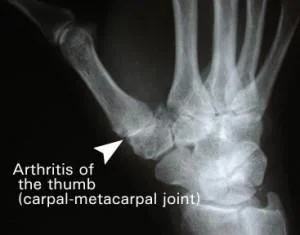

Osteoarthritis

- May affect MCP joint of thumb